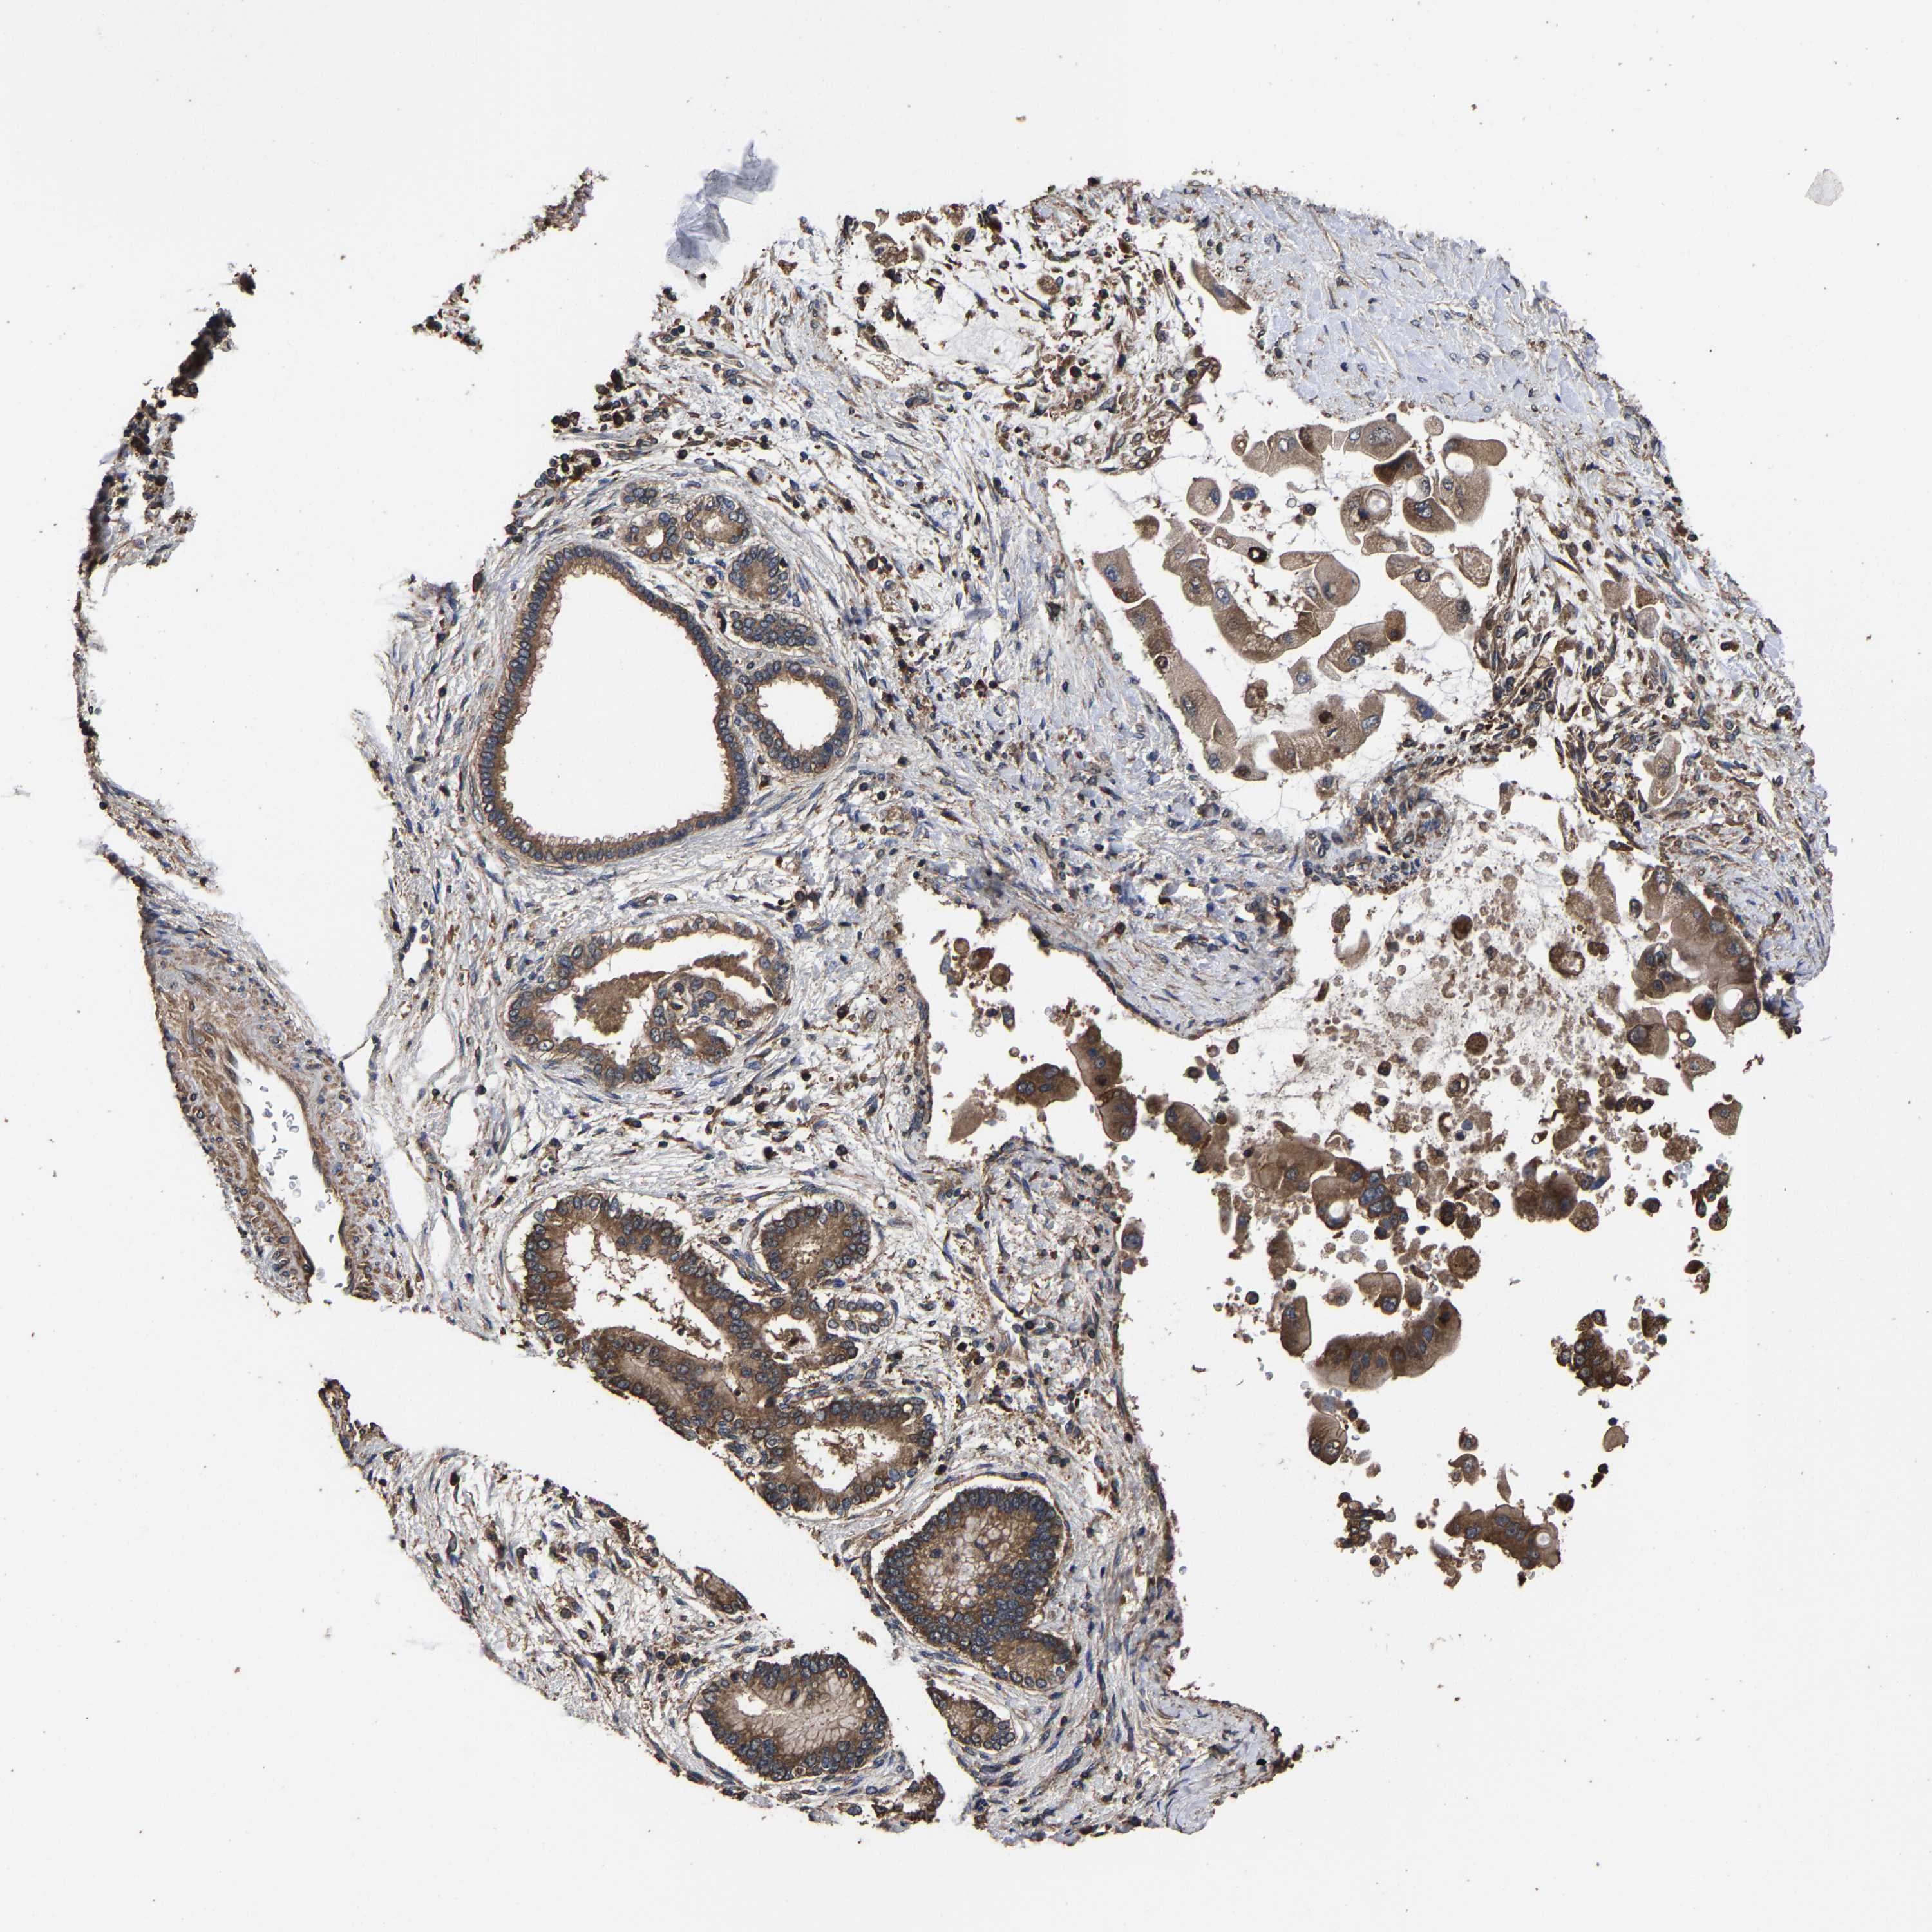

LIVER CANCER